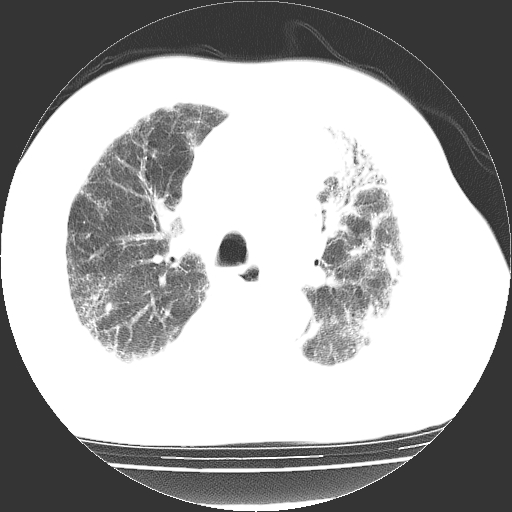

男,68岁,咳嗽、胸闷、发烧三天,查体:双肺散在湿罗音。

首先考虑特发型肺间质纤维化;两侧少量胸腔积液。

依据:1、两肺广泛条索状、网格状、蜂窝状改变。

双肺多发条索状、网格状及小灶状密度增高影。考虑慢支合并感染.间质纤维化,双侧少量胸腔积液

两肺广泛条索状、网格状、蜂窝状改变。肺间质纤维化,肺心病,双侧胸腔积液